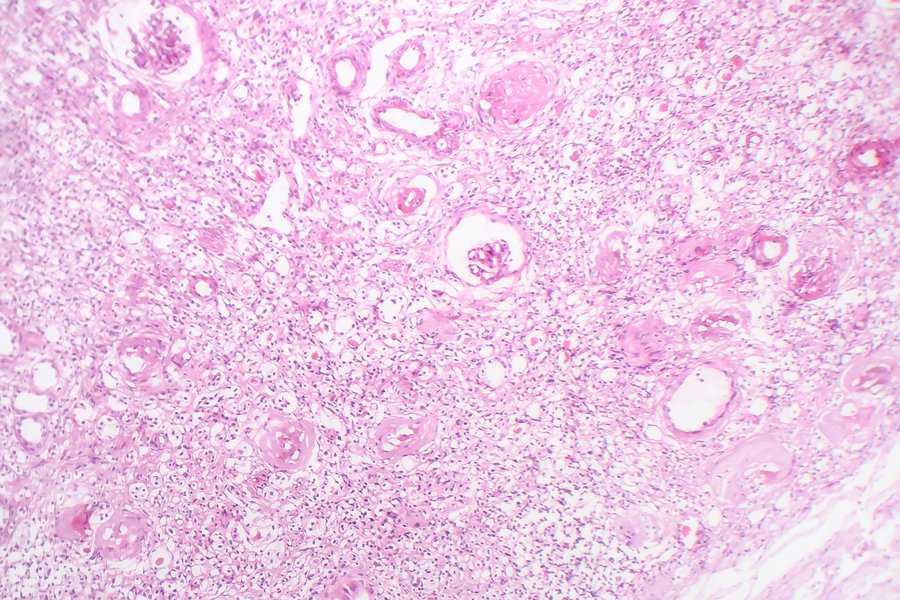

11. Kidney

This image is a light micrograph of a contracted kidney displayed under a microscope. It doesn’t really resemble anything, certainly not a kidney.